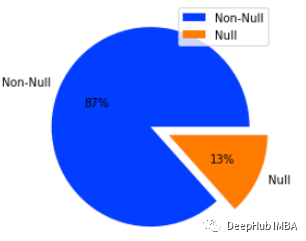

在发现列中大约有13%的空值。我们将删除在结果列中具有空值的行,因为没法用随机的结果填充空值。并将其转换为小写,删除垃圾词